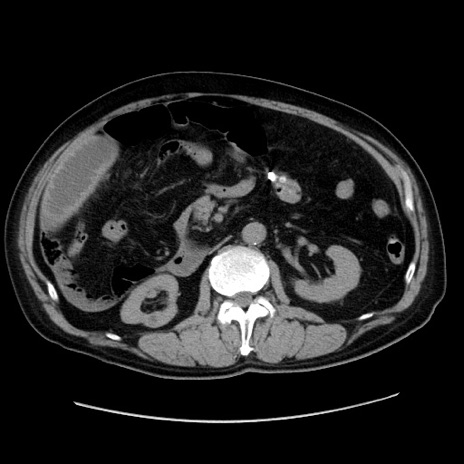

冠状断像

【症例】80歳代男性

【主訴】臍周囲痛

【現病歴】約6時間前から臍下部痛が出現。次第に腹部膨隆・背部痛も生じてきたため来院。背部痛の場所は変化しない。

【既往歴】腎盂腎炎

【身体所見】意識清明、BT 36.3℃、BP  131/87mmHg、P 87bpm、SpO2 100%(RA)、臍周囲自発痛・圧痛あり、反跳痛なし、自発痛部位に一致して板状硬あり、腹部膨隆、腸雑音減弱、CVA tenderness両側陰性。

【データ】WBC 19600、CRP 0.33